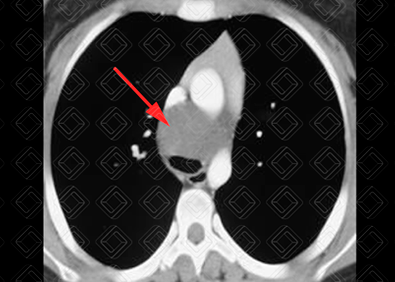

Texto alternativo para a imagem Figura 1. Créditos: Dra. Elazir Mota - Rio de Janeiro/RJ

Descrição da figura 1: Tomografia computadorizada do tórax (janela de mediastino). Lesão ovalada, hipodensa, com densidade cística, localizada no mediastino, próxima à carina, sem comunicação com a árvore traqueobrônquica, porém causando efeito compressivo da mesma.